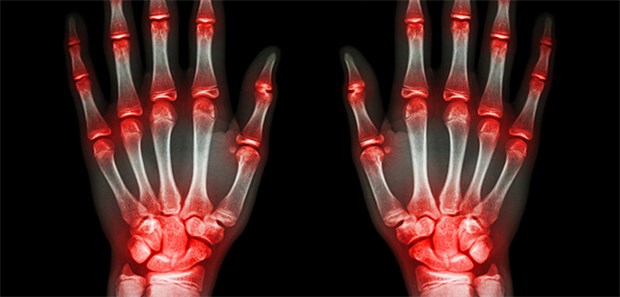

Die Diagnose Fibromyalgie ist nicht immer ganz einfach zu stellen.

© Arco Images / picture-alliance

US-Studie

Wird die Fibromyalgie-Diagnose überstrapaziert?